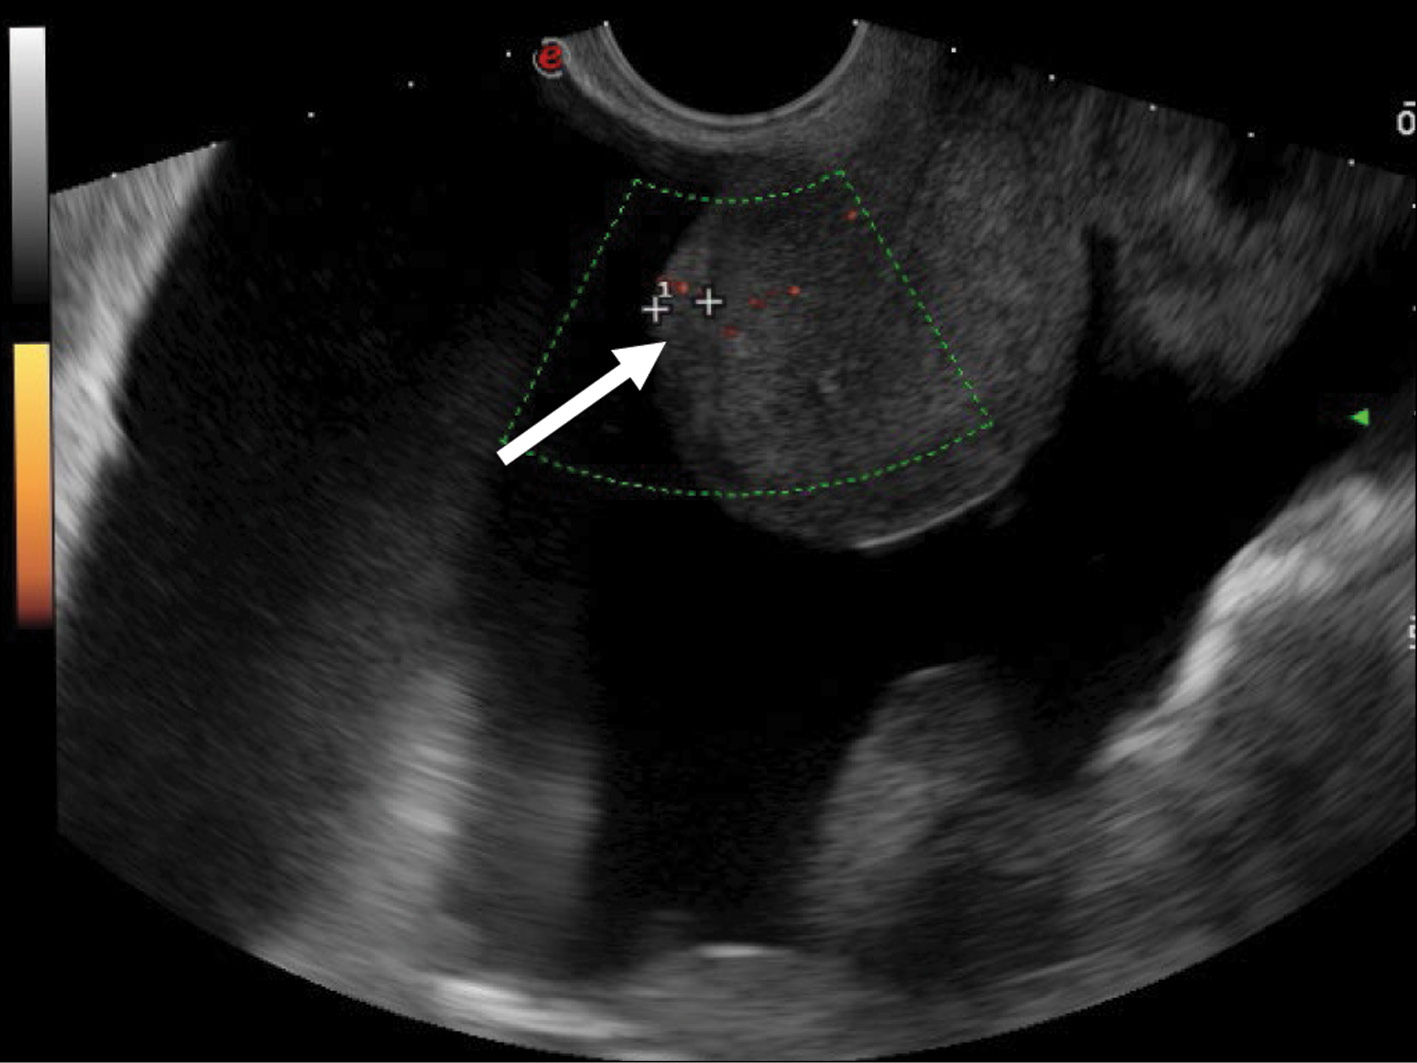

To identify specific US signs of malignant struma ovarii, recurrent tumor lesions along the peritoneum of the malignant struma in one patient were compared with recurrent lesions of serous ovarian adenocarcinoma in 12 patients. When comparing the tumor lesions in the retrouterine space, a more pronounced neoangiogenesis was noted in the tumor lesion of the malignant struma ovarii, where the peak systolic velocity (PS) was recorded in small lesions (4–12 mm) and ranged from 2 to 9 cm/s. The maximum vascular resistivity index (RI max) was 0.53. No blood flow was noted in recurrent lesions along the pelvic peritoneum of the serous adenocarcinoma up to 9 mm, and in lesions up to 15–20 mm, PS varied from 2 to 4 cm/s or was <2 cm/s (Figs. 5 and 8).

Fig. 8. Dopplerography (energy mode) of the tumor lesion along the peritoneum in the retrouterine space in a patient with stage IIIC serous ovarian cancer.

Herein, we compared recurrent lesions of malignant struma and serous ovarian cancer. The recurrent lesions of malignant struma were similar in structure to serous ovarian cancer and had an isohypoechoic structure; however, US angiography and US-CT did not record blood flow in 4–5 mm lesions of the serous ovarian cancer. In this case, we did not register blood flow in the 4-mm lesion of serous ovarian cancer in the pelvic peritoneum. Moreover, Ranade et al. [19] reported peritoneal strumosis (struma peritonei) by US in a patient 6 years after surgical treatment of stroma ovarii, and the lesion had a mixed structure with calcifications.